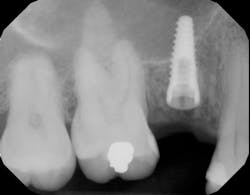

Although restorative and laboratory correction is possible, the best method continues to be prevention—i.e., placing the dental implant in the proper position at the time of surgery.3 Many clinicians still use freehand placement for single- and multiple-unit implant placement, and even with guided surgery, care must be taken when using information from perioperative radiographs to guide the surgical procedure. When taking guide pin radiographs during implant surgery, if the x-ray tube is not perpendicular to the radiographic film/sensor and the depth gauge, distortion of the image may occur (figure 1). This is especially important in a patient with limited opening and at the corners of the mouth in the canine area as there is a higher potential in these areas for alignment error.

Appropriate alignment of the x-ray beam is a critical factor in obtaining clear and accurate radiographic images, reducing distortion, and improving diagnostic quality during dental implant osteotomy preparation. When diagnostic radiographic data transfer is accurate, the dental implant has a higher probability of being placed appropriately (figures 6 and 6a).